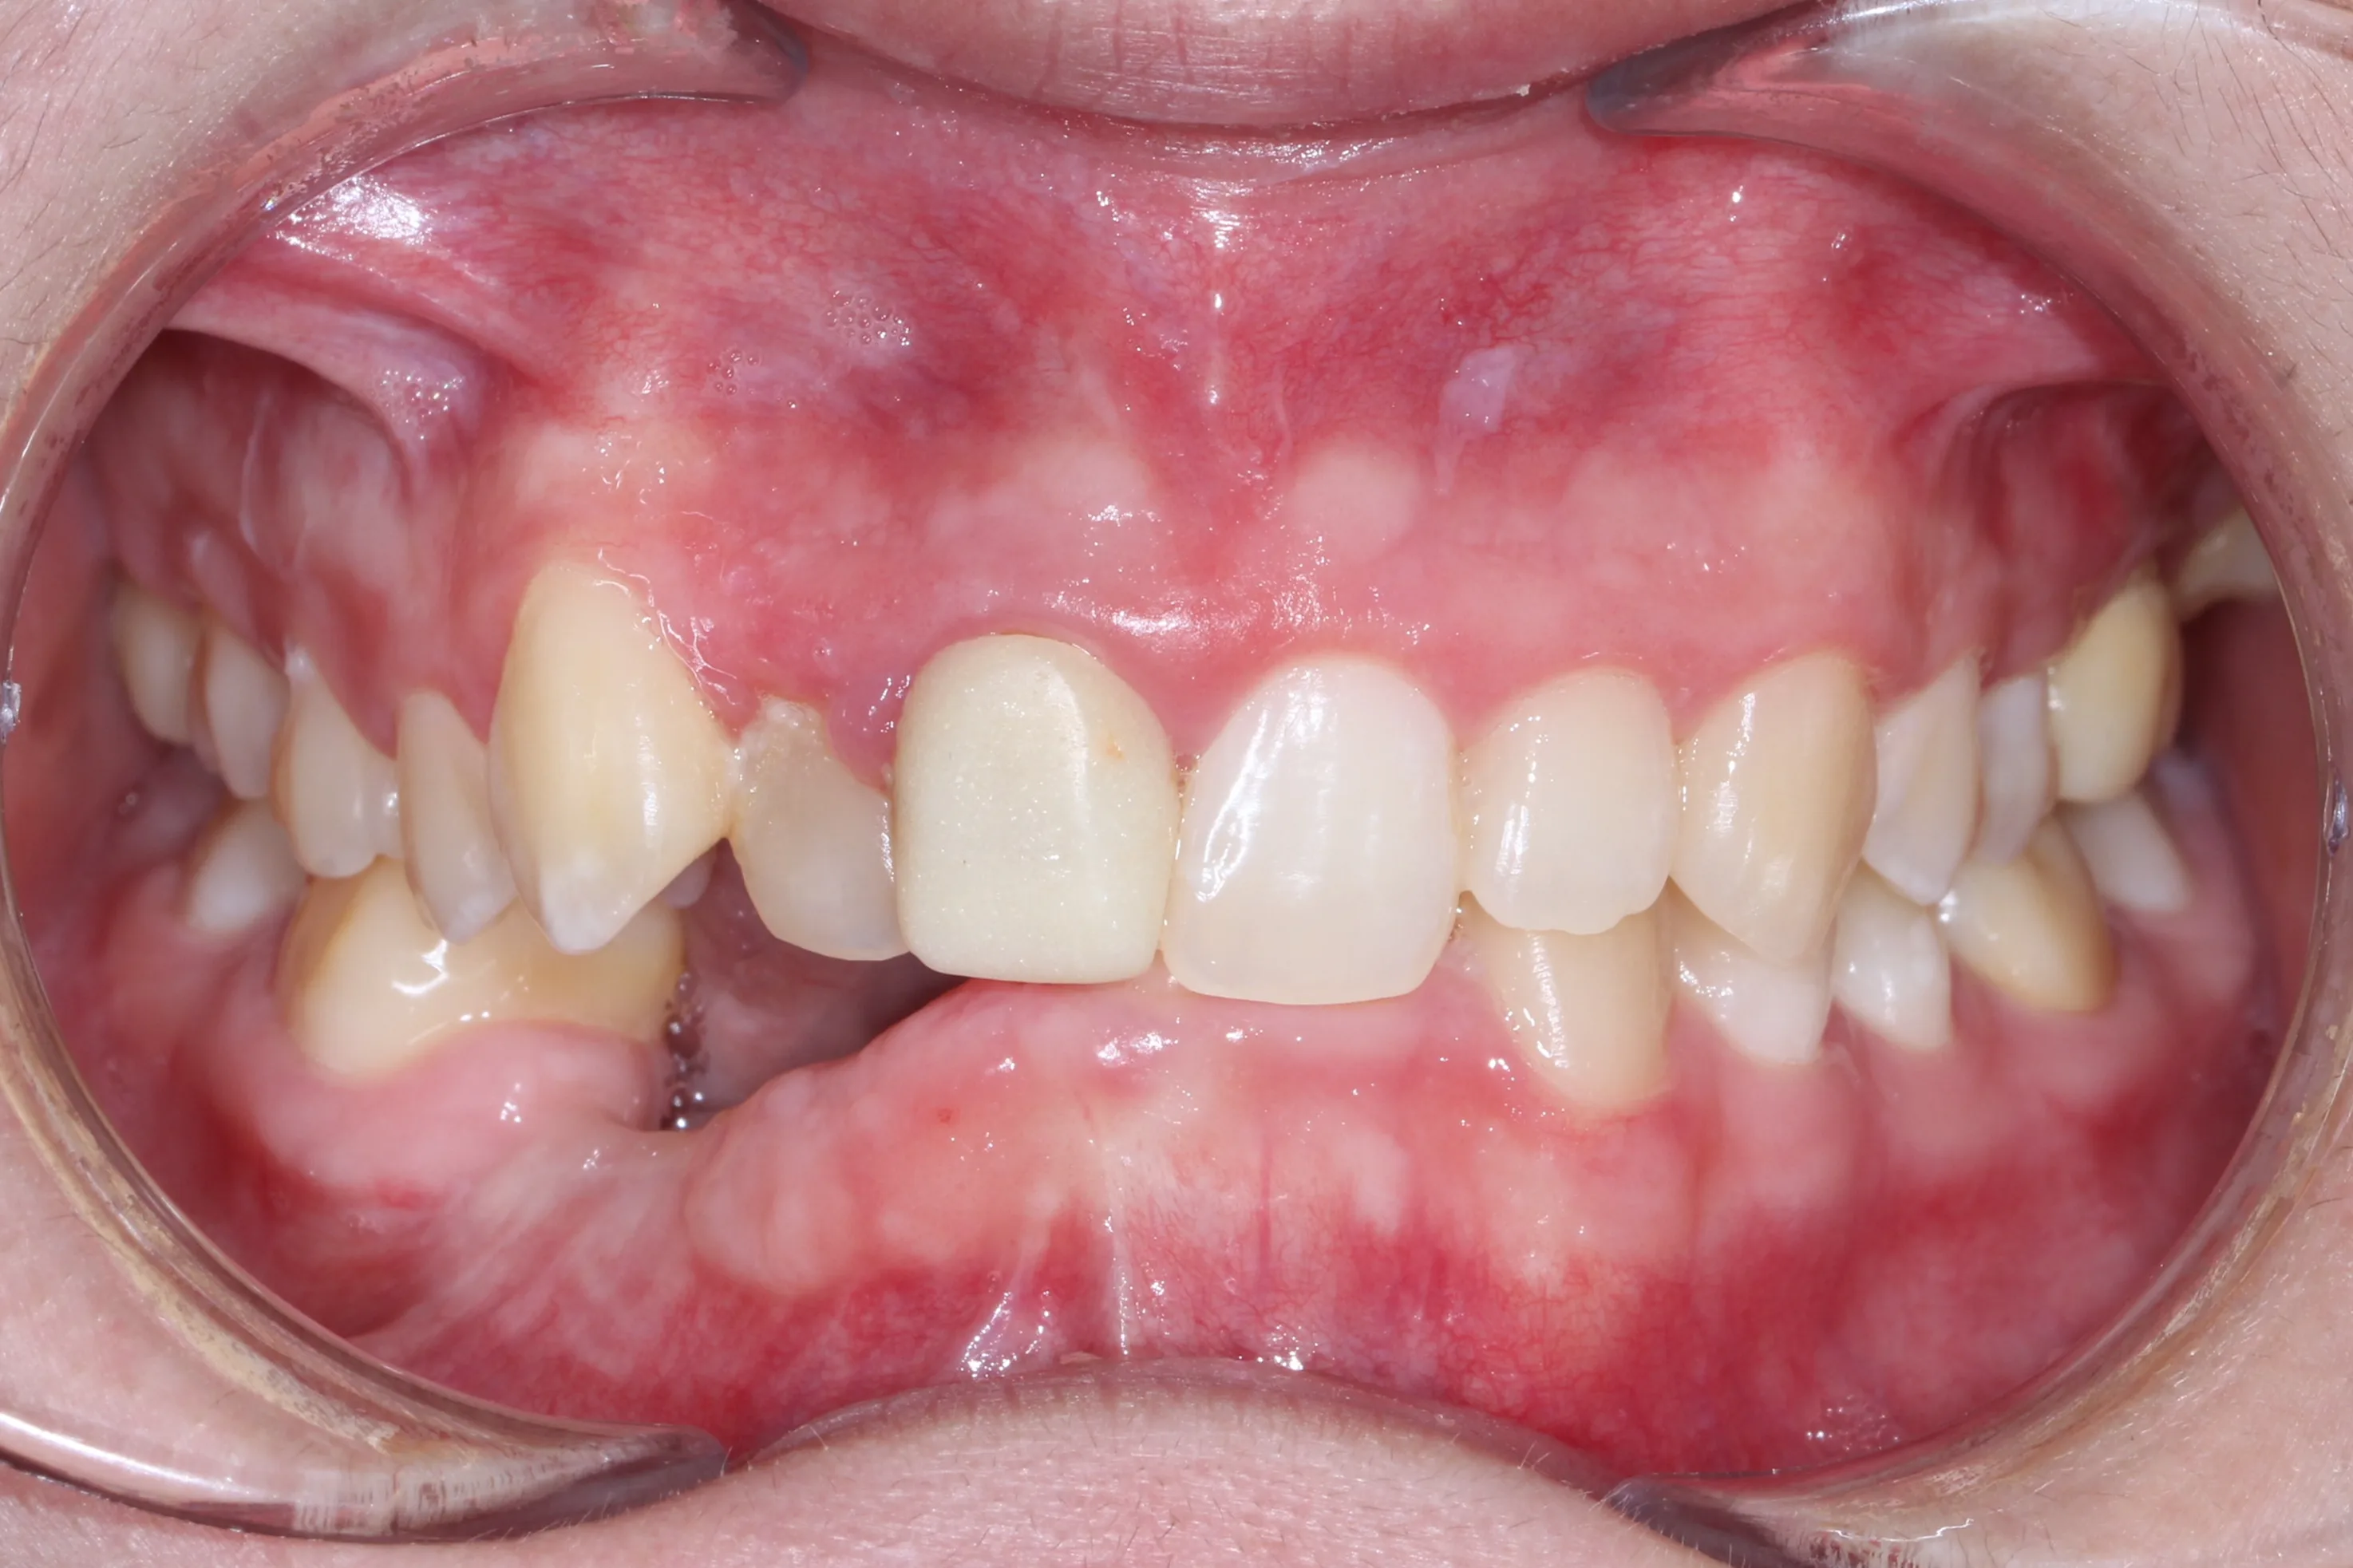

만 21세 환자로, 기존에 사고로 여러 치아를 다치고 상실한 상태로 매우 심한 교합무너짐이 있었습니다.

치료전 (Before)